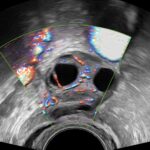

Sistema ecografico per ostetricia, ginecologia e fertilità

VOLUSON S8 con Touch panel

- 3D Uterine Trace

- Immagini veloci chiare e uniformi

- Dettaglio e risoluzione di contrasto eccezionale

- Visualizzazione dei piccoli vasi e dei bordi nel cuore fetale con RadiantFlowTM

- HDlive: tecnologia di rendering 3D/4D di Voluson che trasforma i dati ecografici in immagini più realistiche con profondità, illuminazione e texture migliorate